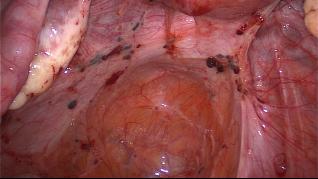

Der Goldstandard zur Erfassung einer intraabdominalen Endometriose ist die Laparoskopie. Dabei können endometrioseverdächtige Bereiche nicht nur bioptisch zur histologischen Sicherung entnommen werden, sondern mit einem therapeutischen Ansatz auch entfernt werden.

Die Laparoskopie ist nicht nur der Goldstandard zur Diagnosestellung, sondern gleichzeitig auch der geeignete Zugang für eine operative Therapie. Der Erfolg ist jedoch stark von der klinischen und technischen Erfahrung des Operateurs bzw. der Operateurin abhängig. Peritoneale Endometrioseherde werden entweder mit dem CO2-Laser evaporisiert oder, vor allem grössere Bezirke, exzidiert. Endometriome bis zu einer Grösse von 4 cm sollten exzidiert oder eröffnet und die Zystenwand mit dem CO2-Laser evaporisiert werden. Bei Endometriomen, die > 4 cm sind, kann ein zweizeitiges Vorgehen mit Biopsie und Drainage anlässlich der ersten Operation, Therapie mit Gestagenen für drei Monate und anschliessender second look Laparoskopie mit Evaporisation der Zystenwand diskutiert werden.

Bei Befall des Septum rectovaginale ist eine Behandlung nur erfolgreich, wenn eine radikale Exzision des befallenen Gewebes erfolgt. Auch nach Durchführen einer präzisen Bildgebung ist das wirkliche Ausmass des Endometriosebefalls oft erst intraoperativ zu erkennen. Eine urogenitale Endometriose ist selten und betrifft nur ca. 1 bis 2 % aller Fälle von Endometriose. Bei der tief infiltrierenden Endometriose ist in ca. 12 % der Fälle der ableitende Urogenitaltrakt ebenfalls befallen. Deshalb sind präoperativ die ableitenden Harnwege speziell zu untersuchen und die Operateure bereit, die entsprechenden Pathologien zu behandeln.